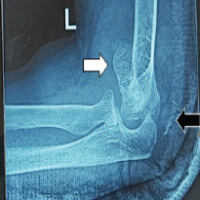

The patient underwent conservative management with regular physiotherapy to maintain joint mobility and analgesics for pain relief. Surgical excision of the ossified tissue was not performed to allow HO to mature. Gradual improvement in knee function over the following months was observed. At 1-year follow-up, full knee extension was obtained; however, restricted flexion was present with no significant improvement observed (Fig. 3 and 4). The patient was advised to undergo excision at the end of 1 year. Following excision, radiotherapy with a single cycle of 75cGy was given in the immediate post-operative period. Chemoprophylaxis with indomethacin 75 mg given once daily for 3 months and discontinued. The wound healed well, and the patient showed symptomatic improvement with a 20° increase in ROM during the initial post-operative period (Fig. 5). At 8 months post-excision, there is no radiographic evidence of recurrence (Fig. 6), and the range of knee flexion has further improved to 80°. The patient remains symptomatically more comfortable following the excision.

HO is the development of bone in tissues where it normally does not develop and, often, after surgical trauma, inflammation, or local tissue injury [5]. In TKR, surgical manipulation, disruption of the periosteum, and soft-tissue trauma can all set up an environment for ectopic bone formation, primarily through osteoinductive factors such as bone morphogenetic proteins and inflammatory cytokines. HO occurrence after TKR is less common, with the reported prevalence from 1% to 3%. The patient had limited knee flexion and pain on occasion from the HO impinging against the quadriceps mechanism, an extremely rare and unusual complication. Most patients have asymptomatic or very mild stiffness post-TKR, so this presentation was unique. Without identifiable predisposing factors, such as prior HO, trauma, or systemic conditions, the patient had severe functional limitations that demonstrate the unpredictable behavior of HO. Early detection is key in the management of HO, and this was exemplified by the progressive imaging findings in this case. There was a hazy appearance at 5 weeks post-onset that progressed to well-formed ossification at 3 months. These findings underscore the value of routine post-operative follow-up to detect complications early and intervene appropriately. Conservative management strategies range from physiotherapy, analgesics, and/or medications such as indomethacin or bisphosphonate to maintain mobility of the joint as well as limit further ossification [7]. Prophylactic radiotherapy offers a potential option to inhibit further ossification, but its application post-diagnosis remains debated. Current evidence supports its use within a narrow window-either preoperatively or immediately postoperatively-rather than after ossification has formed [8]. Immediate surgical excision of HO diagnosed early is generally not recommended, as immature ossification carries a higher risk of recurrence and bleeding. Waiting for the ossification to mature, typically over 6–12 months, allows for better demarcation of the mass and reduces the risk of surgical complications. Surgical excision is best reserved for cases of mature HO that cause significant pain or functional limitations, as it provides better outcomes and minimizes recurrence risks [9]. In this case, operative treatment was effective after a period of 1 year, so that the patient could obtain satisfactory recovery with full extension and increased flexion compared to pre-operative status (Fig. 5 and 7).